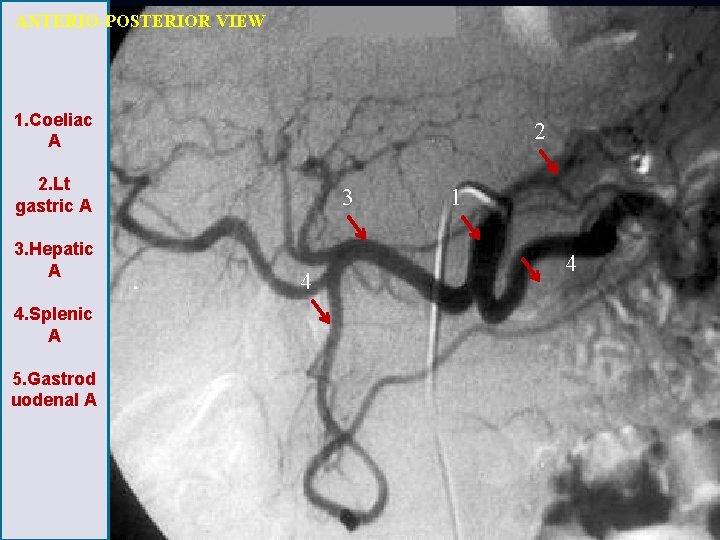

ANTERIO-POSTERIOR VIEW 1. Coeliac A 2 2. Lt gastric A 3. Hepatic A 4. Splenic A 5. Gastrod uodenal A 3 4 1 4